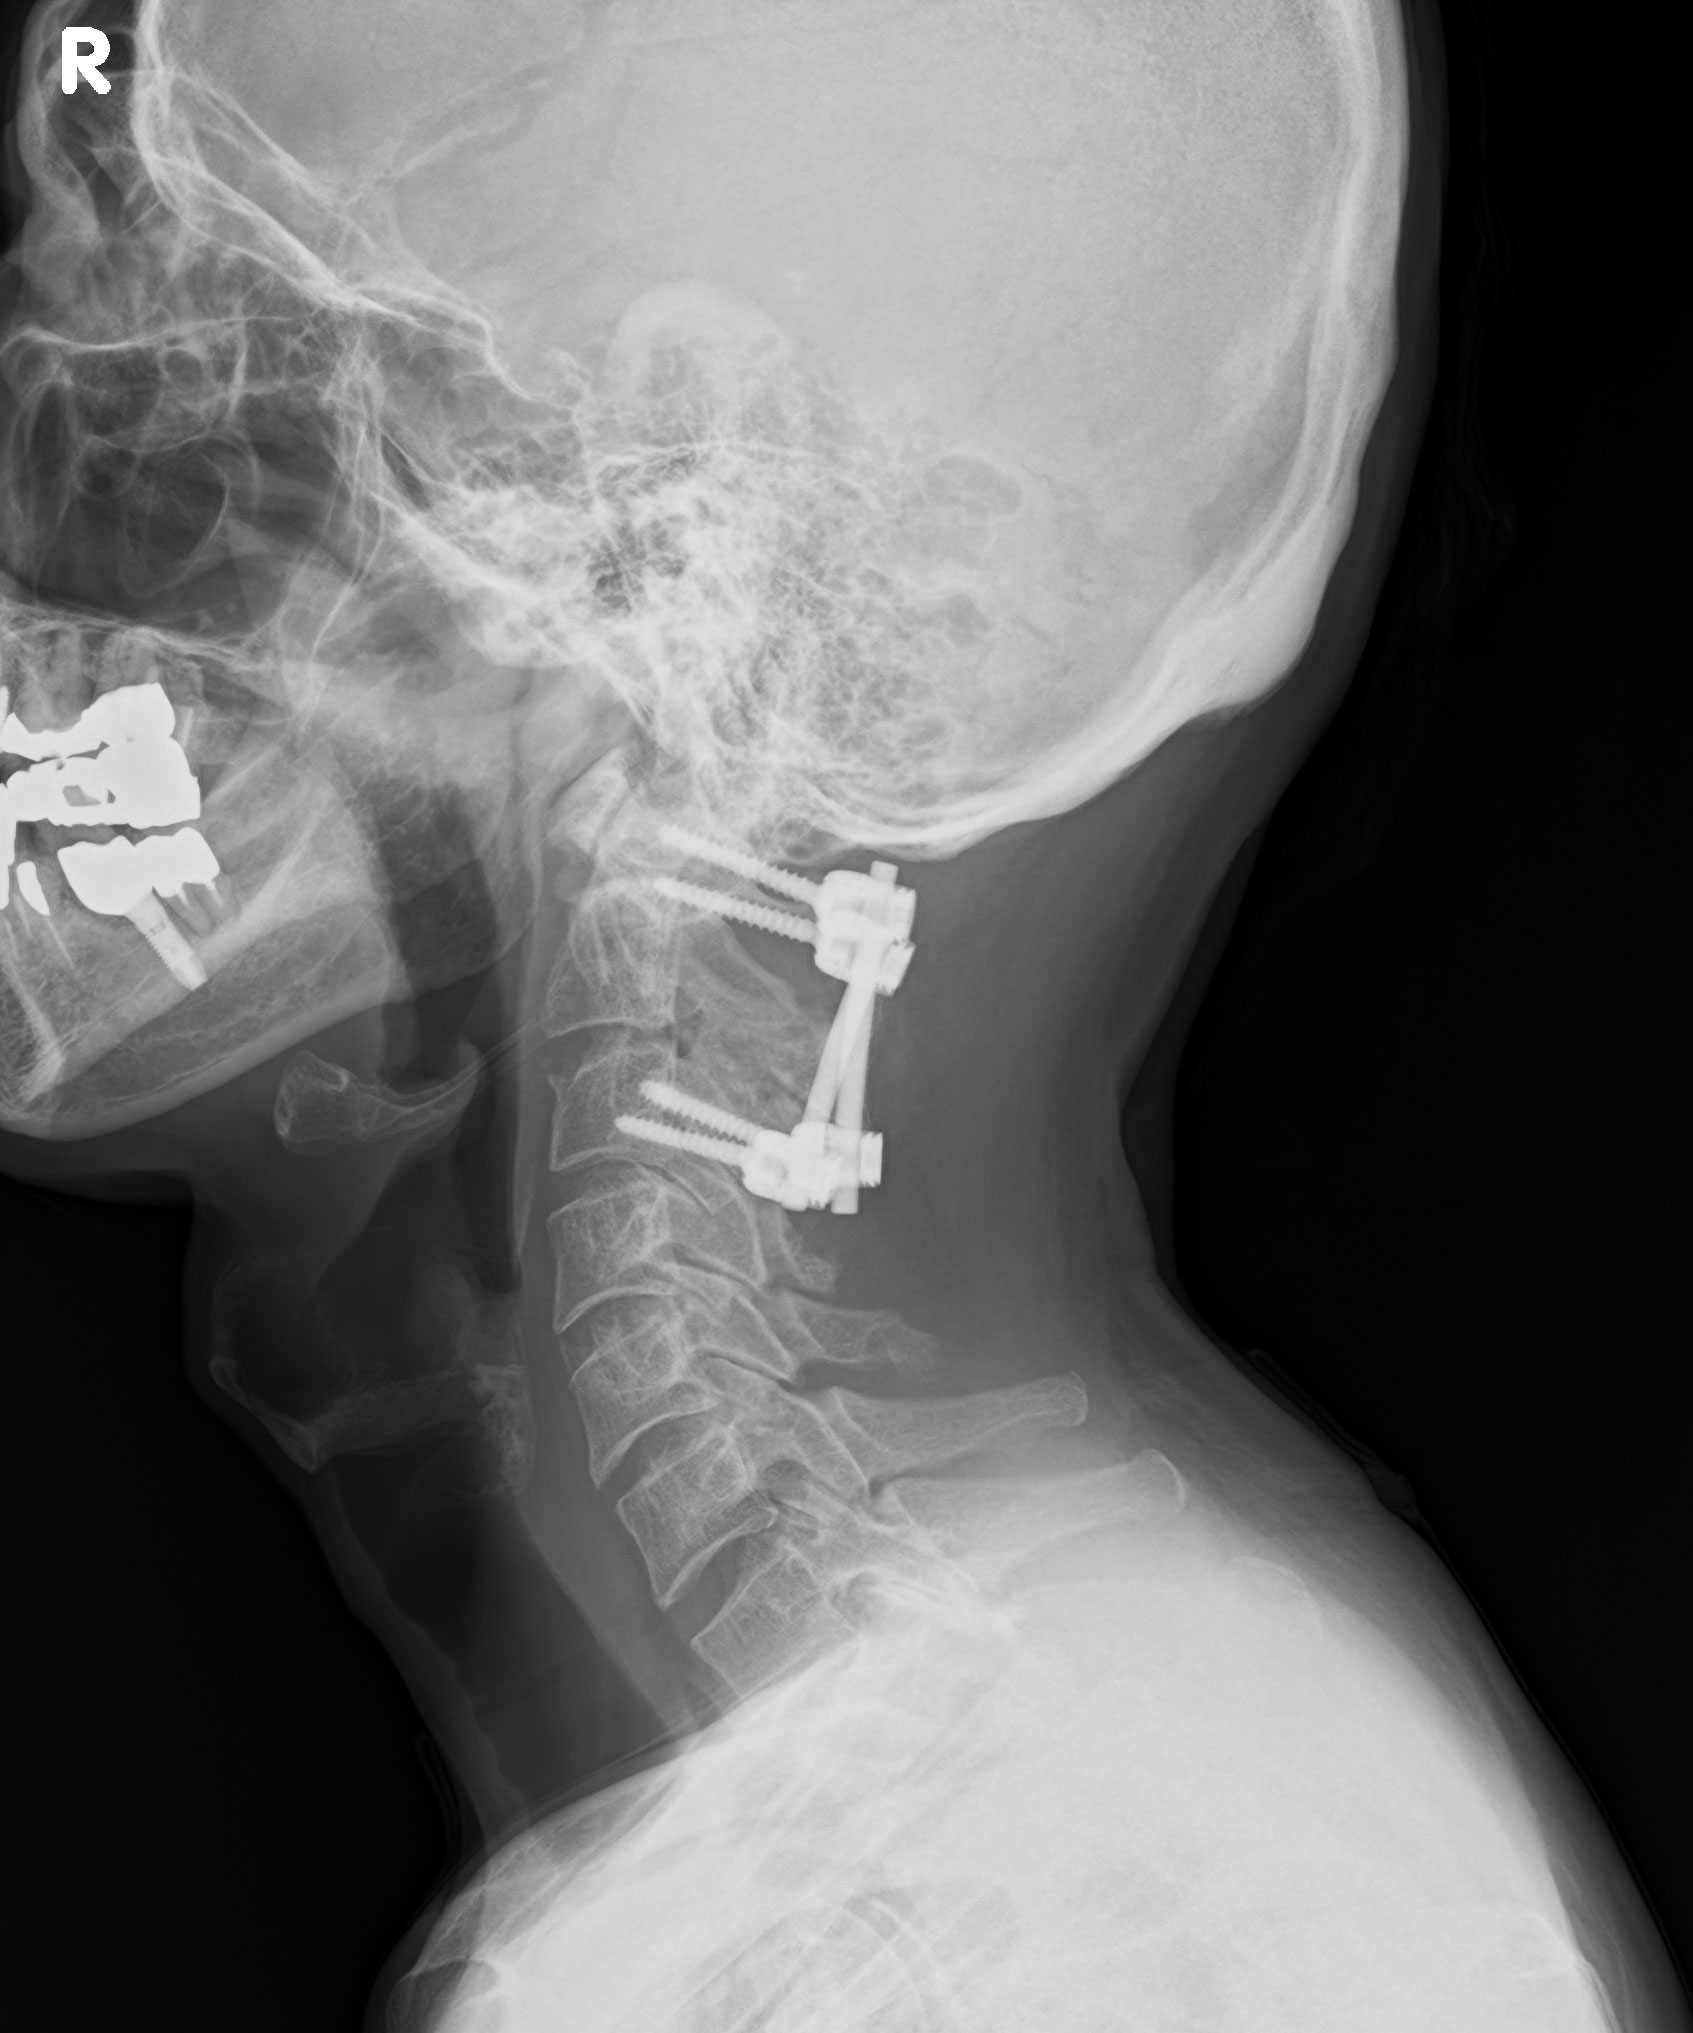

・首の中心から少し外れた場所を背骨が見えるまで皮膚を切り、開く。

・頚椎の脱臼を治す。元の位置に医師が手を使用し戻したとのこと。

・骨折により足りない骨を補充するため、骨盤の骨をとる。腰にメスが入る。

・第2第3の頚椎をつなげる。どこかに骨盤の骨を取り付けたらしい。

・第1第3の頚椎をプレートで固定する。

レントゲンで頚椎を固定したプレートが動いてないことを確認される。

プレートが装着されたままだと、首の左右と上むきの動きが制限される。